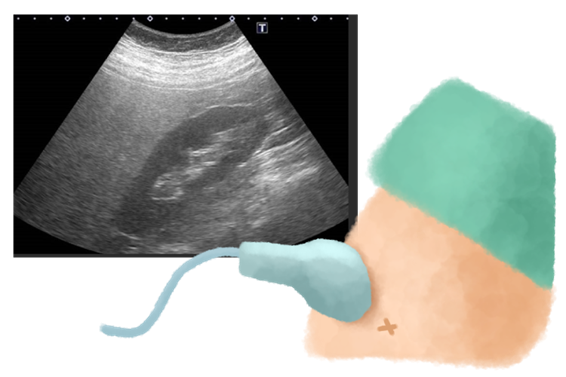

肝硬度測定は、超音波(エコー)を用いて肝臓の硬さを非侵襲的(体に負担をかけずに)に評価する検査です。

肝硬度測定は、腹部エコー検査の延長で施行でき、痛みや放射線被ばくの心配もなく、わずか3分程度で完了します。さらに、肝硬度測定では、肝臓全体のおよそ500分の1程度の肝臓の線維化を評価できます。

肝硬度測定では、超音波を用いて肝臓の硬さ(肝硬度)の近似値を求めます。

- 経過観察に最適:硬さが数値化されることで、ダイエットの成果や治療効果がわかりやすく、患者さんのモチベーションアップにもつながります。当院では部位を変えて5回測定し、その平均値を計算しています。